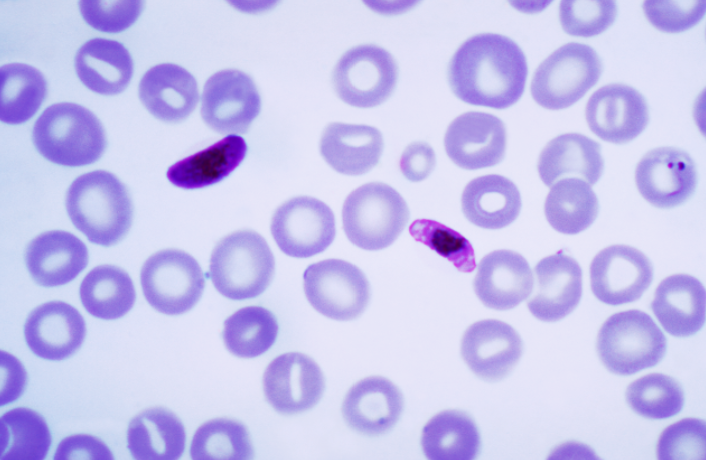

Plasmodium falciparum

Plasmodium falciparum

Plasmodium falciparum